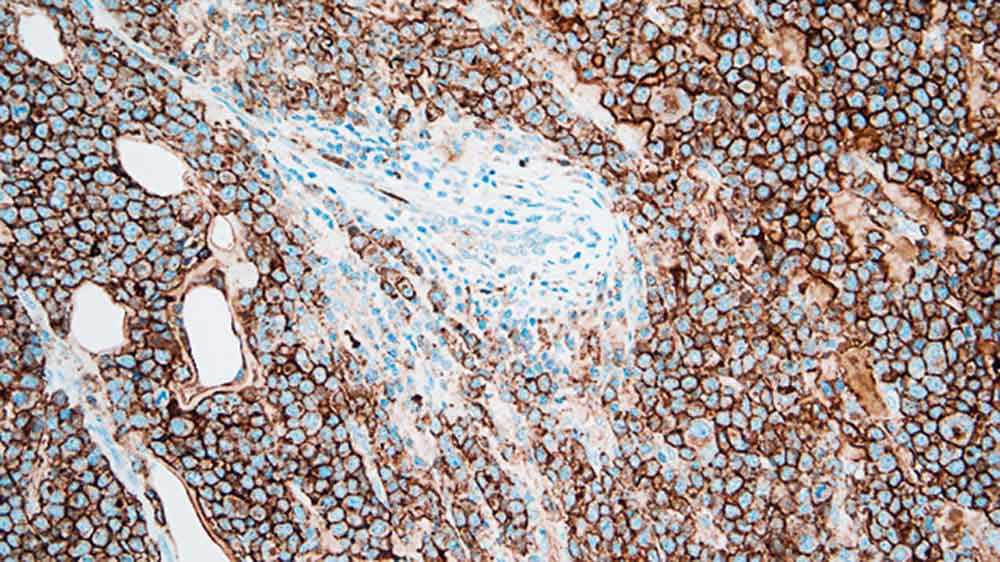

Plasmacytoma: immunohistochemical staining for CD138. Note the intense membrane staining of tumor cells. CD138: clone MI15

CD138は、重層および単層上皮に加えて、プレB細胞、未熟B細胞、免疫グロブリンを産生する形質細胞といった正常リンパ球の異なる分化段階に発現する膜貫通型ヘパラン硫酸糖タンパクです。子宮頸部の発癌初期では異型細胞におけるCD138発現が消失すると報告されており、CD138の発現は上皮の形態・分化の保持と密接に関連します。免疫組織化学マーカーとしてのCD138の主な有用性は、形質細胞の数量化にあります。